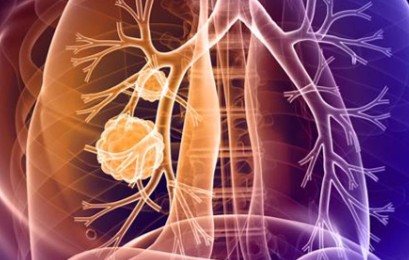

폐암은 초기 자각 증상이 뚜렷하지 않아 굉장히 진행된 상태에서 발견되는게 대부분입니다.. 그렇지만 조기 폐암은 매우 작은 부분만 절제해도 치료가 가능하며 생존율이 70~90%에 이른다.

폐암 증상에는 기침, 체중 감소 흉통, 혈담 즉 피가 섞인 가래, 호흡곤란 등이 있지만, 위 증상은 다른 폐 질환에서도 나타날 수 있는 증상으로 구분하기가 어렵다. 그리고 폐암 초기에는 특별한 증상이 없는 경우가 대부분이라서 최근 흡연뿐 아니라 미세먼지 등 여러가지 요인으로 폐암이 발생하는 경우가 많아 정기검진으로 조기에 발견하는 것이 중요며 폐암 검진을 위해서는 특히나 저선량 흉부 CT를 촬영하는 것이 좋다라고 전문가들은 말하고 있습니다..